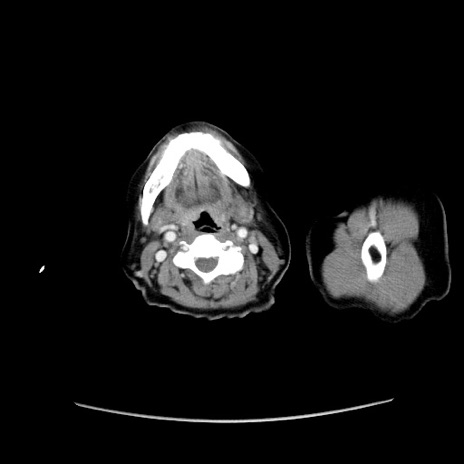

症例19(横断像)

【症例】80歳代女性

【主訴】下腹部痛

【現病歴】約8時間前より下腹部痛の出現あり、救急外来受診。

【既往歴】両側付属器切除

【身体所見】意識清明、下腹部正中に手術痕あり、その部位に一致して圧痛と反跳痛あり。腸蠕動音は亢進。

【データ】WBC 9300、CRP 0.15